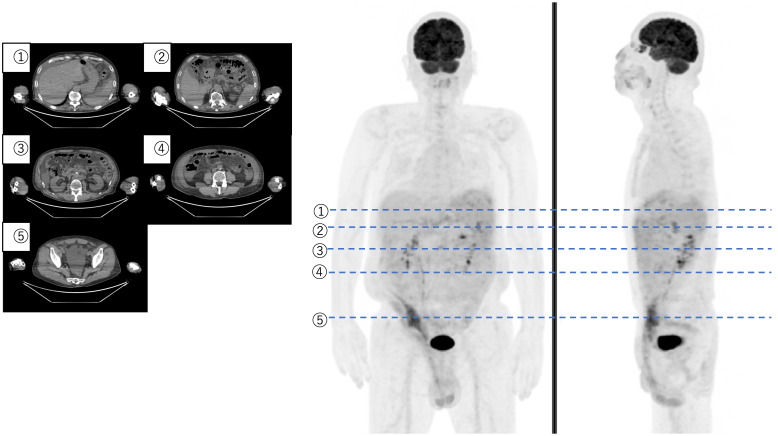

An aggressive case of Fluid overload-associated large B-cell lymphoma (FO-LBCL) with CD20 down-regulation.

CD20下调的侵袭性液体超载相关大b细胞淋巴瘤(FO-LBCL)病例